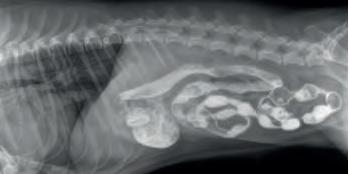

Steiner og kjøttbein i magesekken er lett å se på røntgenbilder. Andre ting som vi har funnet i magesekken hos hund som f.eks. porsjonsbokser for leverpostei er mindre røntgentett og krever bruk av kontrastmiddel for å få de frem på et røntgenbilde. I de fleste tilfeller kan vi da gå ned med et endoskop (lang slange med kamera i enden) og fange fremmedlegeme i en «kurv» og dra det forsiktig opp.

En hund på 10 mnd kom inn på klinikken med kronisk oppkast. Røntgen med kontrast viser en ring i magesekken som gir mistanke om fremmedlegeme (bilde 1)

Eier savnet toppen av en lekekong og det kunne samsvare med funn på røntgen. I stedet for å åpne magesek ken kirurgisk brukte vi videoskop, fant fremmedlegeme i magesekk (bilde 2), fanget den i «kurven» og dro den skånsomt opp fra magesekken (bilde 3). Dette til stor glede for både hund og eier!